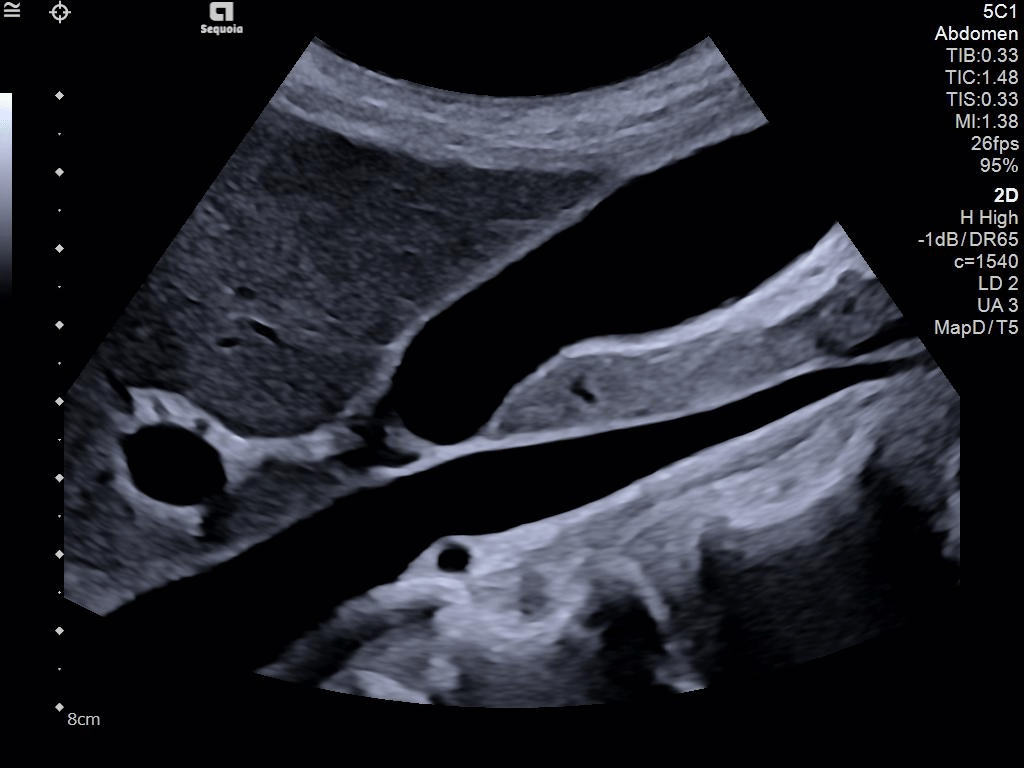

A clearer, deeper perspective with optimal acoustics for each clinical use case. Expand your assessment with advanced tools that take ultrasound beyond its traditional role.

- AI Abdomen automatically recognizes and labels 17 anatomical views and 12 routine measurements.